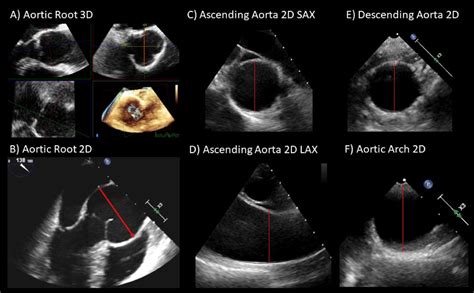

Physicians generally categorize the aorta into four distinct zones for diagnostic purposes:

• Aortic Root: The segment attached to the heart valve.

• Ascending Aorta: The portion rising upward from the heart.

• Descending Thoracic Aorta: The portion traveling down through the chest.

• Abdominal Aorta: The terminal portion located below the diaphragm.

Diagnostic Guidelines for Normal Aorta Diameter

Determining the Normal Aorta Diameter is typically done using non-invasive imaging technologies like Echocardiography, Computed Tomography (CT) scans, or Magnetic Resonance Imaging (MRI). Generally, a measurement in the abdominal aorta that exceeds 3.0 cm is considered the upper limit of normal, whereas anything above 5.0 cm in the thoracic region often triggers clinical concern.